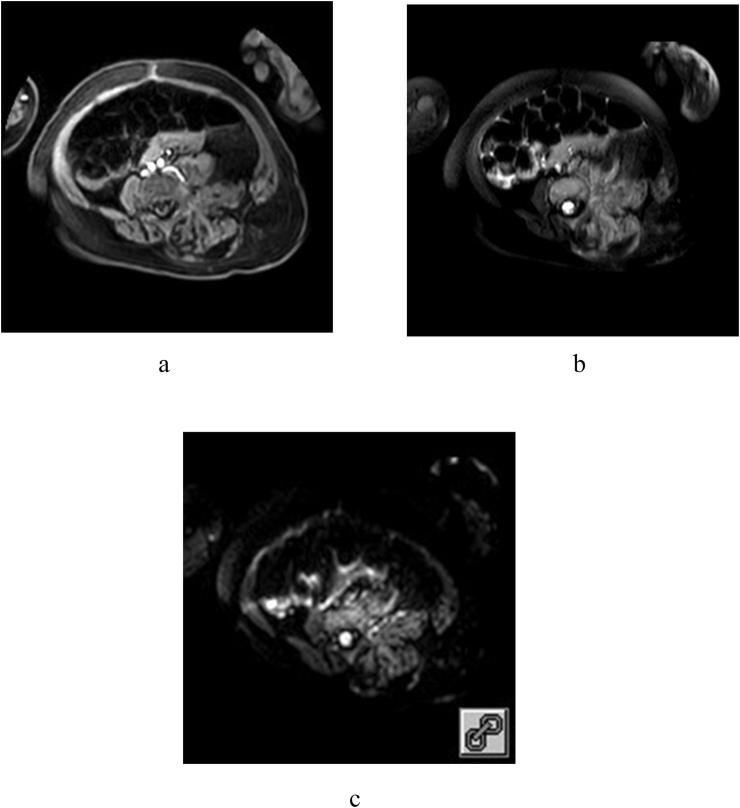

The mean age of the 27 patients was 105 ± 80.27 days. Twenty-two (81.5%) of these patients had Kasabach-Merritt phenomenon. Most KHEs were located in the trunk and/or extremities (22/27). Ultrasonography showed heterogeneous echogenicity and/or striated hypoechoic bands with abundant or patchy blood flow within the tumor. On plain computed tomography (CT), they appeared as heterogeneous lesions isodense with the muscles, with a CT value of 29.58 ± 11.53 HU. In the arterial phase, the KHEs showed striated or lamellar heterogeneous enhancement, with a CT value of 153.91 ± 52.11 HU after enhancement. All KHEs showed uneven and high signal intensity on T2-weighted imaging, mixed high and low signal intensity on fat-saturated images, and no significant diffusion restriction on diffusion-weighted imaging.

KHEs can occur in various locations and present as highly infiltrative and heterogeneous masses that can invade the skin, adjacent muscles, and bones. A vascularized mass with purpuric skin changes, with uneven and high T2WI signal is highly suggestive of the diagnosis of KHE.

27例患者的平均年龄为105±80.27天。其中22例(81.5%)患者出现卡萨巴赫-梅里特现象。大多数KHE位于躯干和/或四肢(22/27)。超声检查显示肿瘤内部回声不均匀,可见条纹状低回声带,血流丰富或呈片状。平扫计算机断层扫描(CT)显示病变与肌肉等密度,密度不均匀,CT值为29.58±11.53 HU。动脉期,KHE呈条纹状或片状不均匀强化,强化后CT值为153.91±52.11 HU。所有KHE在T2加权成像上均表现为不均匀高信号,在脂肪抑制图像上呈高低混合信号,在扩散加权成像上无明显扩散受限。

KHE可发生于不同部位,表现为高度浸润性、不均匀的肿块,可侵犯皮肤、邻近肌肉和骨骼。出现皮肤紫癜改变的血管化肿块,T2WI信号不均匀且高,高度提示KHE的诊断。